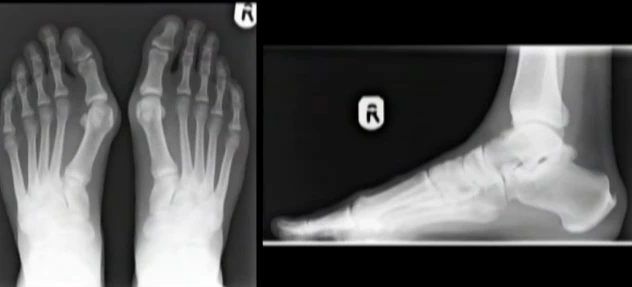

Phần xương chân bị tổn thương do đi giày cao gót được minh họa bằng hình ảnh 3D.

Từ những minh họa 3D này, các chuyên gia đều khuyến cáo phụ nữ chỉ nên đi những đôi giày cao gót vừa phải.

Điều này sẽ khiến bàn chân bị đau và tổn thương kéo dài, đặc biệt nếu thường xuyên sử dụng giày cao gót.

Đi giày cao gót khiến đôi chân bạn không được tự do, xương bàn chân bị ép theo khuôn dẫn đến dễ bị dị dạng.